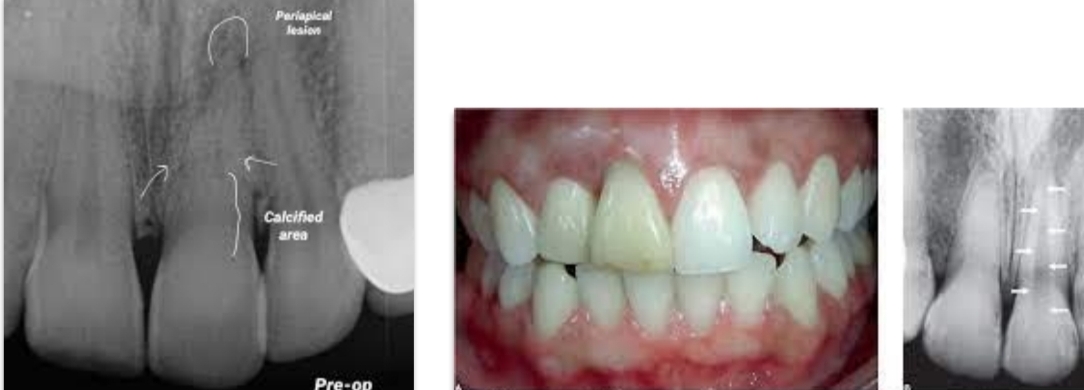

With endo of maxillary central incisor, what may prevent direct access, and what can make access difficult?

Lingual shoulder

Calcific metamorphosis

What is calcific metamorphosis and what appearance can it give the crown?

Tooth’s trauma response - canal partially/completely filled with hard tissue

Yellow discoloration of crown

Dilacerations